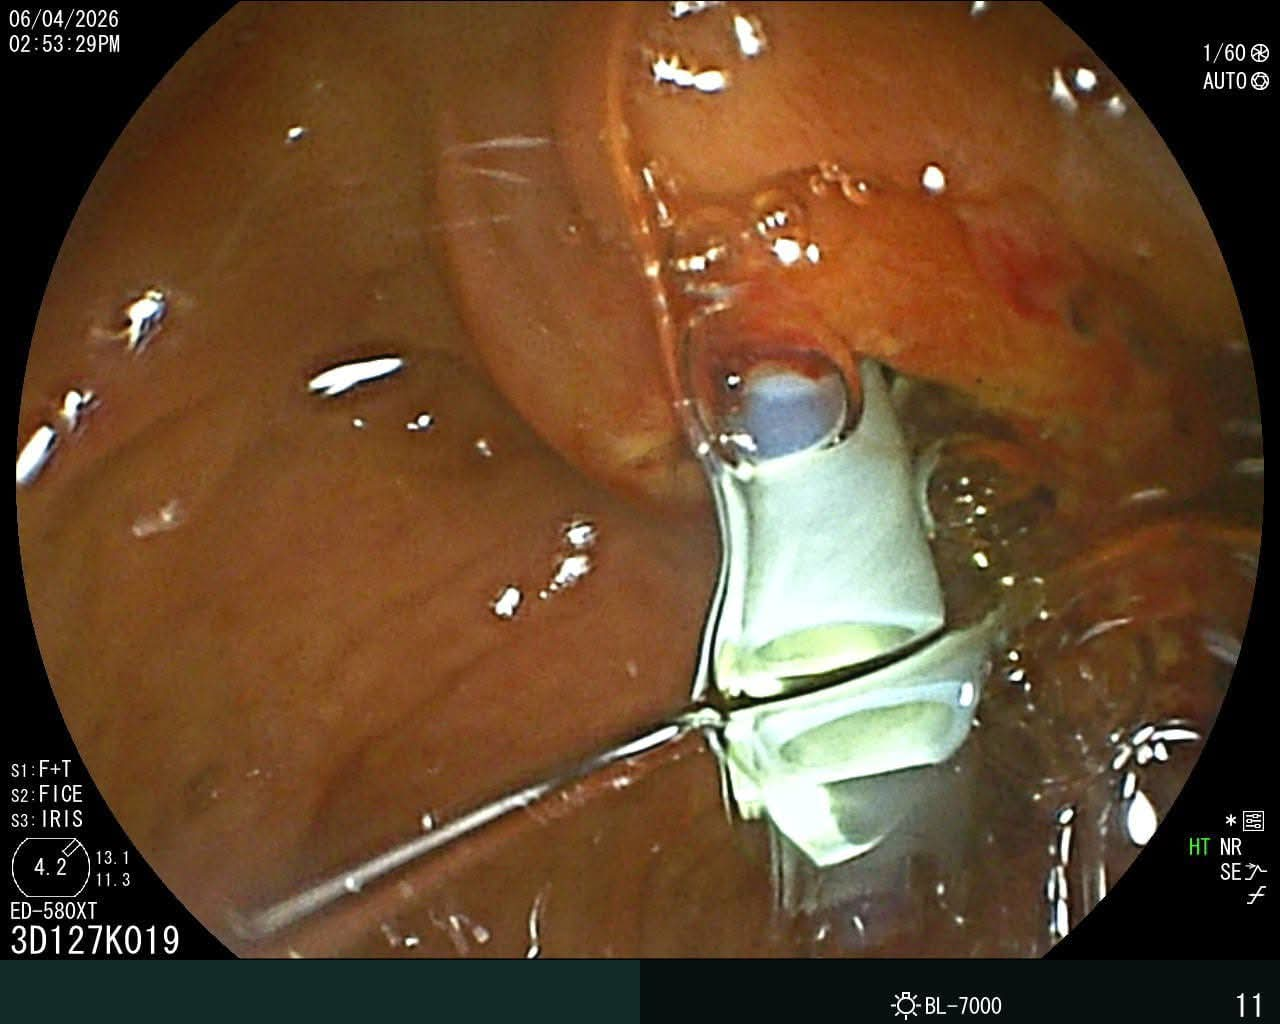

وتمكن الفريق الطبي من إجراء التدخل الدقيق بنجاح، حيث شمل إزالة دعامة من القنوات المرارية، واستخراج حصوة من المرارة، إلى جانب تركيب دعامات جديدة بالقنوات المرارية، بما ساهم في تحسين الحالة الصحية للمريض وتجنب التدخل الجراحي التقليدي.

ويُعد منظار ERCP من الإجراءات الطبية الدقيقة المستخدمة في تشخيص وعلاج أمراض القنوات المرارية والبنكرياس، مثل إزالة الحصوات، وعلاج الانسدادات، وتركيب الدعامات، ما يساهم في تقليل الحاجة إلى العمليات الجراحية، ويُسرّع من وتيرة تعافي المرضى.